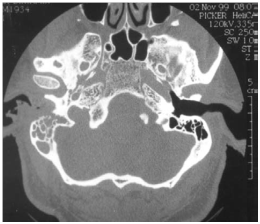

Figure 2 TDM from the rock, axial bone window: lysis of the tympanal bones.

The MEO is an otological infection that has life-threatening complications. It is considered as a complication of external otitis.2 Occurs mainly in the elderly who have diabetes or another condition that compromises the immune system. Doctors must be able to recognize this infection, initiate treatment, and refer patients to an Otolaryngologist. The precise etiology of this condition is unknown, but theories related to impaired immunity, the local tissue microangiopathie and even modified biochemistry of earwax have been proposed. Infection of the soft tissues of the external ear canal is common, especially in hot and humid climates. The usual triggers are trauma (often caused by q-tips) and exposure to the pool of water. The most frequently found germ is Pseudomonas aeruginosa, is not a normal germ of the EEC.3 Other possible germs include Staphylococcus epidermidis,4 gram negative bacteria and fungi. External otitis patients complain of earache and sensitivity to atrial movement. The otorrhoea may be present, the obliteration of the external ear canal by edema and secretions can cause hearing loss, or a feeling of fullness in the ear. The disease comes from the EEC and propagates through the osteo-cartilaginous junction to involve soft tissue under the temporal bone. Granulation tissue is usually present in the EEC. The spread of the infection can cause thrombosis of the lateral sinuses and petrous sinus upper and lower. Initially, the progressive skull base osteomyelitis can cause cranial Polyneuropathy, paralysis of the facial nerve being the most common; cranial nerves IX, X, and XI (the jugular foramen syndrome) nerves and cranial nerve XII (hypoglosse channel) are less often involved with the development of the sphenoidal sinusitis. Imaging to show the extension of the infection to the bony structures is usually required to establish the diagnosis of MEO6 imaging modalities include tomographic (CT) scan, scan bone to the technetium Tc99m medronate methylene diphosphonate, and scintigraphy to Ga 67 gallium citrate. CT is used to determine the location and extent of diseased tissue (Figure 1 & Figure 2). The temporal bone is the first os to be affected, with an imminent involvement of petrous apex and the mastoid process. Extratemporal extension has become rare since the introduction of powerful antibiotics. In evaluating the scanner, it is important to remember that at least one third of the minerals is lost before the radiological changes are becoming apparent; Conversely, the bone remineralization continued long after that infection is Gueriela scan is a diagnostic sensiblemais non-specific to the MEO, if to the 67Ga scintigraphy is available, (Figure 3). It must be used for the initial diagnosis and follow-up tool.7 Using in combination imaging modalities, it is possible to prove that the temporal bone is reached (scan and bone scan to the 99mTc) with infectious process (Ga 67 scintigraphy).6 MRI is of interest in advanced forms allowing a better analysis of the deep spaces of the face, the nervous foramina, merien hard spaces and the Medullary bone in the base of the skull.